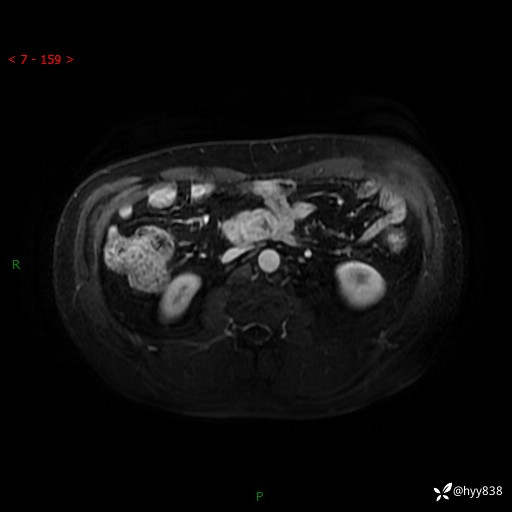

MRI(T1WI+T2WIfs+DWI)

增强